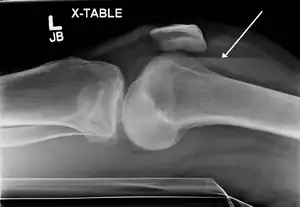

Lipohemarthrosis due to a tibial plateau fracture